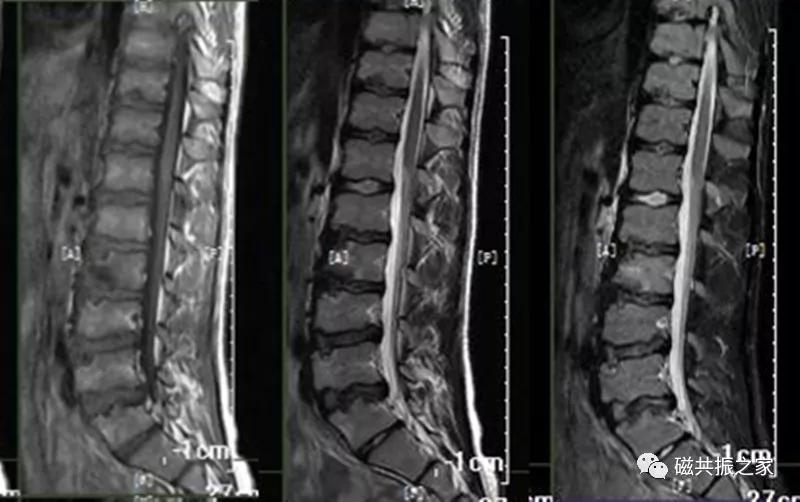

7.腰椎椎体滑脱

脊椎滑脱是指椎体相对下一节椎体向前或后方滑动移位,颈椎、腰椎常见。腰椎以4/5椎体和腰/骶连接部常见。滑脱分为向前和向后滑脱,根据上下椎体的滑动距离分为四度(在矢状位上将椎体上缘分为4等分,对应着1-4度滑脱)。